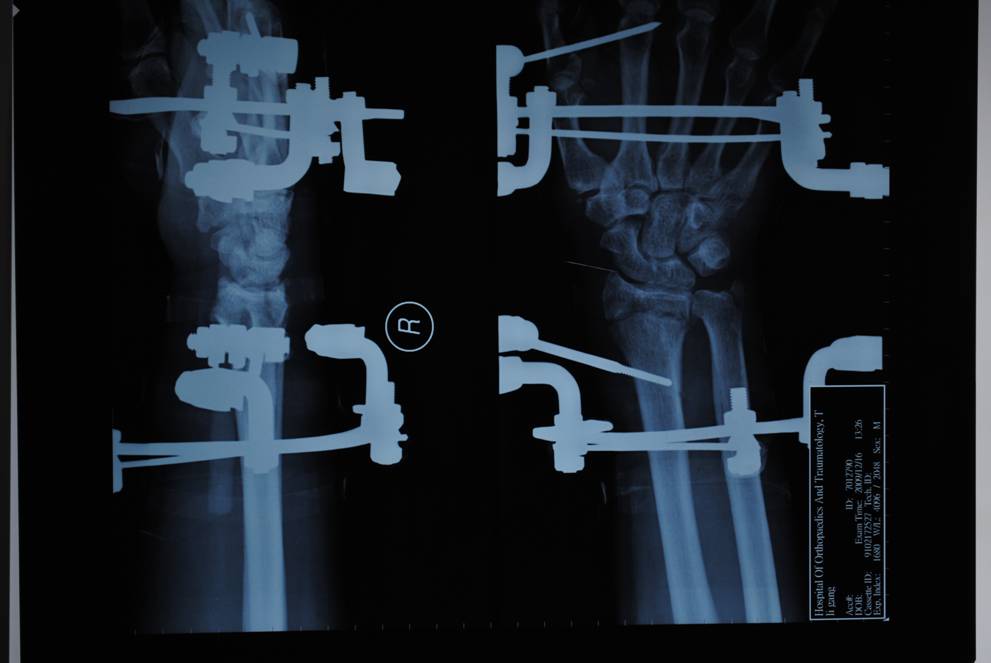

專利腕架

1、一種組合式腕關節(jié)三維牽引固定架,其特征在于:主要包括一根碳纖維和一根硬鋁連接桿和兩只弧型環(huán),兩只弧型環(huán)沿弧線方向的端面上均設有多個通孔,每根碳纖維連接桿的兩端分別鎖緊連接于兩只弧型環(huán)相對應的通孔上,每個弧型環(huán)上均設有兩只鎖針螺釘,鎖針螺釘靠近其螺栓部分的端面上均設有穿針槽,鎖針螺釘的螺栓經螺母鎖緊在弧型環(huán)上,第一克氏針依次穿過第一弧型環(huán)上的第一鎖針螺釘穿針槽、掌骨頸、第二鎖針螺釘穿針槽并由螺母鎖緊第一、二鎖針螺釘的螺栓將第一克氏針壓緊在第一弧型環(huán)上,第二克氏針依次穿過第二弧型環(huán)上的第三鎖針螺釘穿針槽、橈骨、第四鎖針螺釘穿針槽并由螺母鎖緊第三、四鎖針螺釘的螺栓將第二克氏針壓緊在第二弧型環(huán)上。

橈骨遠端骨折術前

橈骨遠端骨折術后

橈骨遠端骨折術前 橈骨遠端骨折術后

五研獨家產品組合式腕關節(jié)骨外定架,具有專利保護

組裝簡便,穿針便捷,適合各種橈骨遠端骨折及腕部矯形。斷端無X線遮擋。